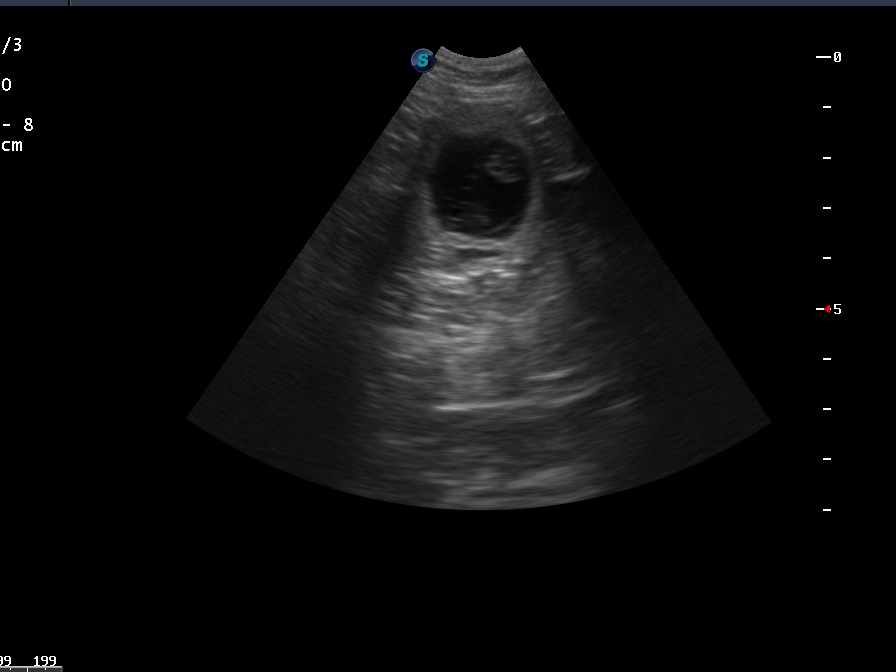

23.03.20 (29.Trächtigkeitstag)